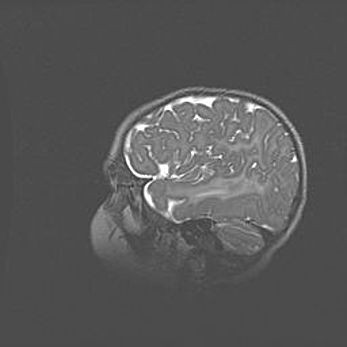

Неполная лизэнцефалия (пахигирия). Открытая гидроцефалия.

Возраст: 17 дней

Вес: 3110 г

Пол: мужской

Окружность головы: 33,5 см

Срок гестации: 35-36 недель

Лизэнцефалия—недоразвитие корковой пластинки и мозговых извилин в результате нарушения миграции нейронов коры. Поверхность мозговых полушарий гладкая. Микроскопически выявляется отсутствие нормальных слоев коры и скопление групп нейронов в подкорковом белом веществе.

Пахигирия—уменьшение числа вторичных извилин. В пораженном полушарии нервные клетки образуют толстый недифференцированный слой с неправильно расположенными нервными волокнами и группами гетеротопных клеток. Нервные клетки незрелые. Белое вещество истончено. При этом нередко аномально развит корково-спинномозговой путь.